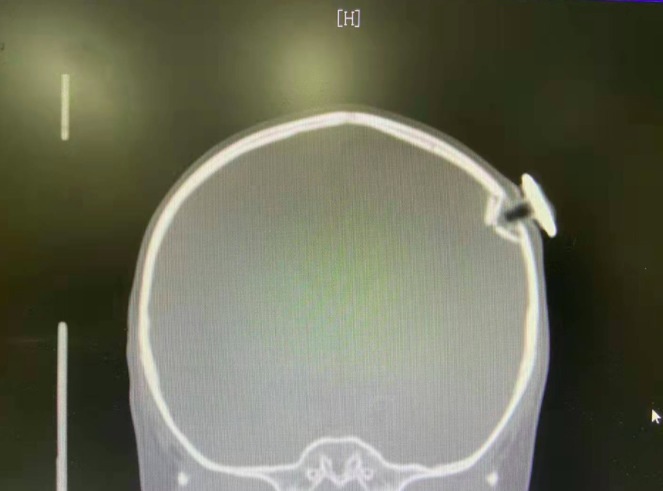

根据CT检查显示

这枚磁力钉撞碎了孩子颅骨

扎进大脑约1.3厘米

造成左侧顶骨凹陷性骨折和脑外出血

而且刺破脑膜

差点就损伤了脑部的功能区